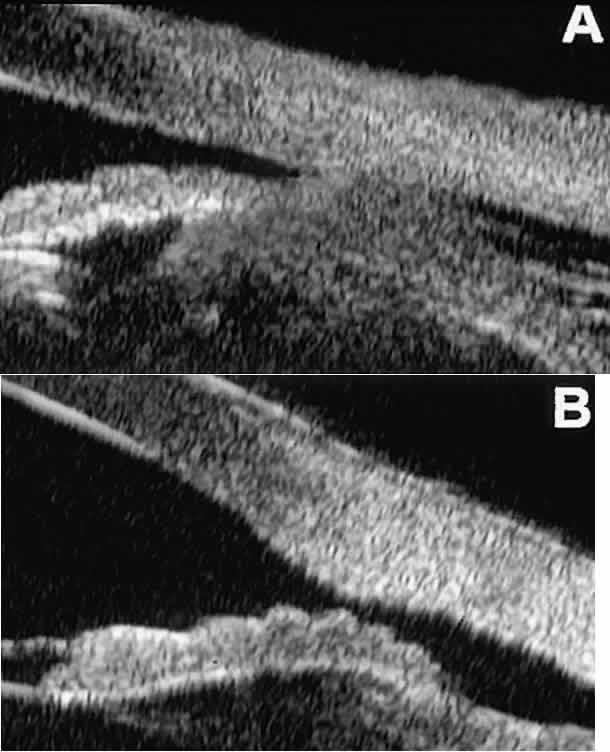

After blunt ocular trauma, UBM can be used to evaluate iris-angle abnormalities associated with and possibly obscured by hyphema, including angle recession and cyclodialysis, and to illustrate the presence and extent of blood clots.4 Angle recession is characterized on UBM (Fig. 21A) by posterior displacement of the point of attachment of the iris to the sclera. In the acute stage, the post-traumatic recess is usually filled with blood. Cyclodialysis (described and illustrated earlier) appears on radial UBM slices through the limbal region (see Fig. 13B) as a fluid-filled cleft between the sclera and ciliary body.13 This abnormality is by definition associated with at least a localized ciliochoroidal effusion.

Fig. 21. UBM features of ocular trauma. A. Angle recession with traumatic hyphema after blunt injury. B. Intracorneal foreign body (rose thorn fragment). Note inflammatory cells in adjacent aqueous. C. Intraocular foreign body (glass fragment in inferior angle).

After ocular perforations, lacerations, and intraocular surgery, UBM can show abnormalities such as retained foreign bodies too small to be imaged by other technologies.3,4 Foreign bodies appear on UBM (Fig. 22A and B) as highly reflective focal lesions that are frequently associated with inflammatory features.

Fig. 22. UBM features of primary neuroepithelial cysts of iris and ciliary body. A. Primary neuroepithelial cyst of iris midzone. B. Primary neuroepithelial cyst of iridociliary sulcus. C. Multiple neuroepithelial cysts of peripheral iris and ciliary body. D. Neuroepithelial cysts of pars plana of ciliary body shown in circumferential slice.